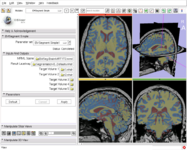

Image:B-spline-reg-detail.png|Improved: [[Modules:RegisterImages-Documentation-3.6|Expert Automated Registration]] (Casey Goodlett) | Image:B-spline-reg-detail.png|Improved: [[Modules:RegisterImages-Documentation-3.6|Expert Automated Registration]] (Casey Goodlett) | ||

Image:PETCTFusion.png| [[Modules:PETCTFusion-Documentation-3.6 |PETCTFusion]] (Wendy Plesniak) | Image:PETCTFusion.png| [[Modules:PETCTFusion-Documentation-3.6 |PETCTFusion]] (Wendy Plesniak) | ||

Improved: Expert Automated Registration (Casey Goodlett)

PETCTFusion (Wendy Plesniak)